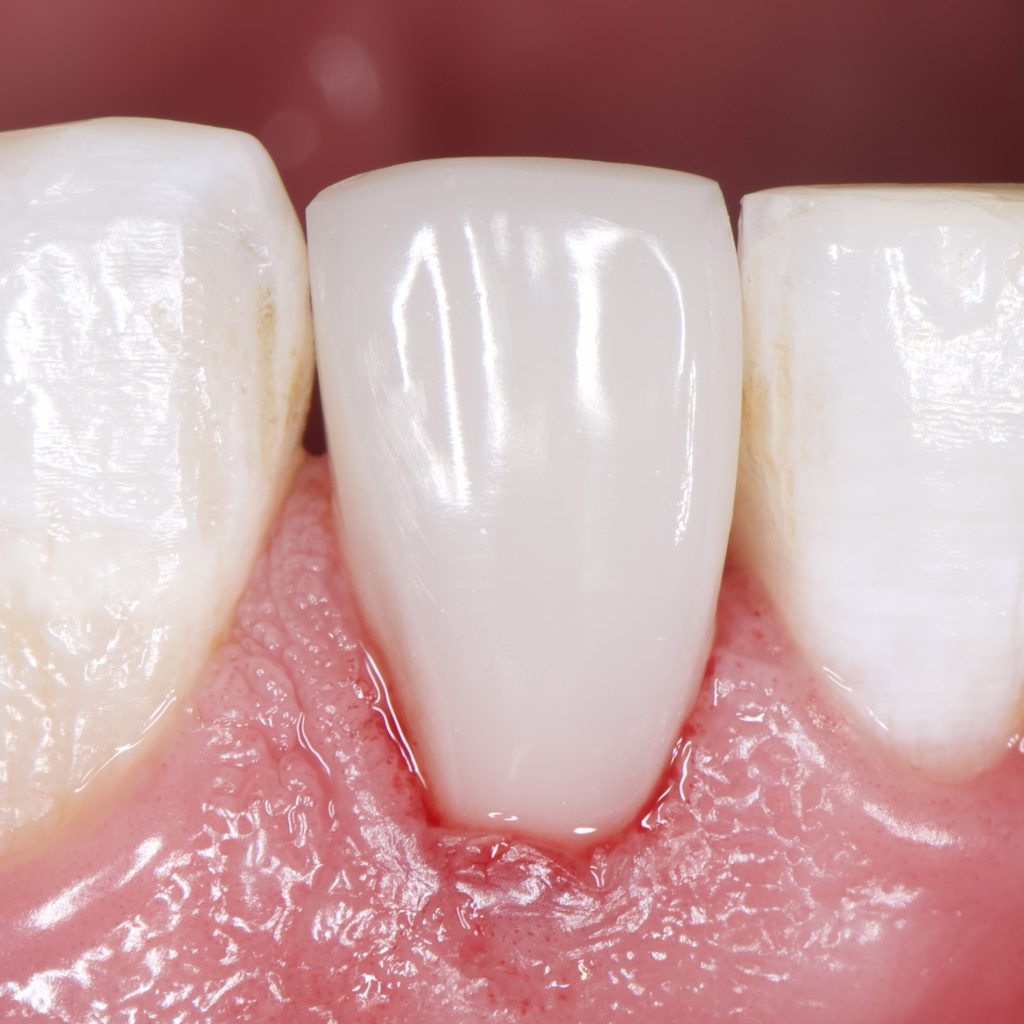

1 month Follow up